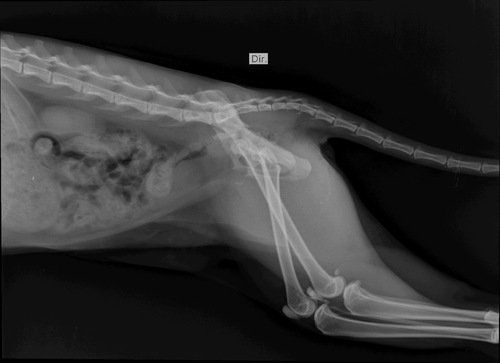

Preciso arrecadar esse valor para realizar a cirurgia da Cora! Ela caiu do 6° andar e precisa da cirurgia com urgência para poder defecar e urinar, pois quebrou o osso da pélvis e teve uma luxação!